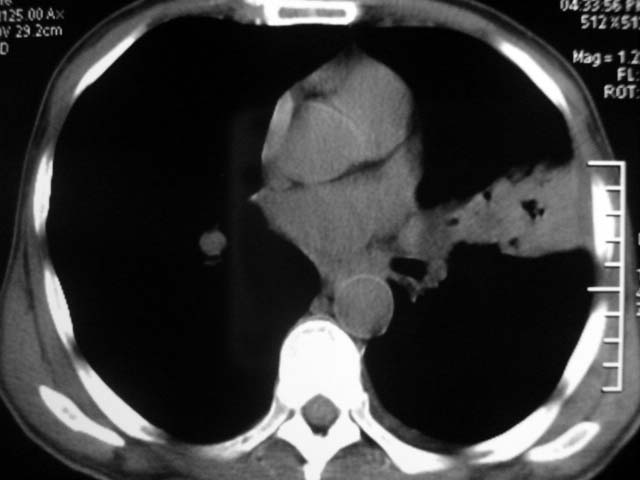

男,52岁,发热2月,糖尿病史。

抗结核治疗irpz方案,血糖未治疗,空腹15.9左右。症状无好转,左胸痛。

复查ct

2、双肺见多发片状及结节状高密度影,大多数病灶中心均见“空泡征”。

3、纵隔内淋巴结肿大。

结果:两肺继发性肺结核并曲霉菌感染。